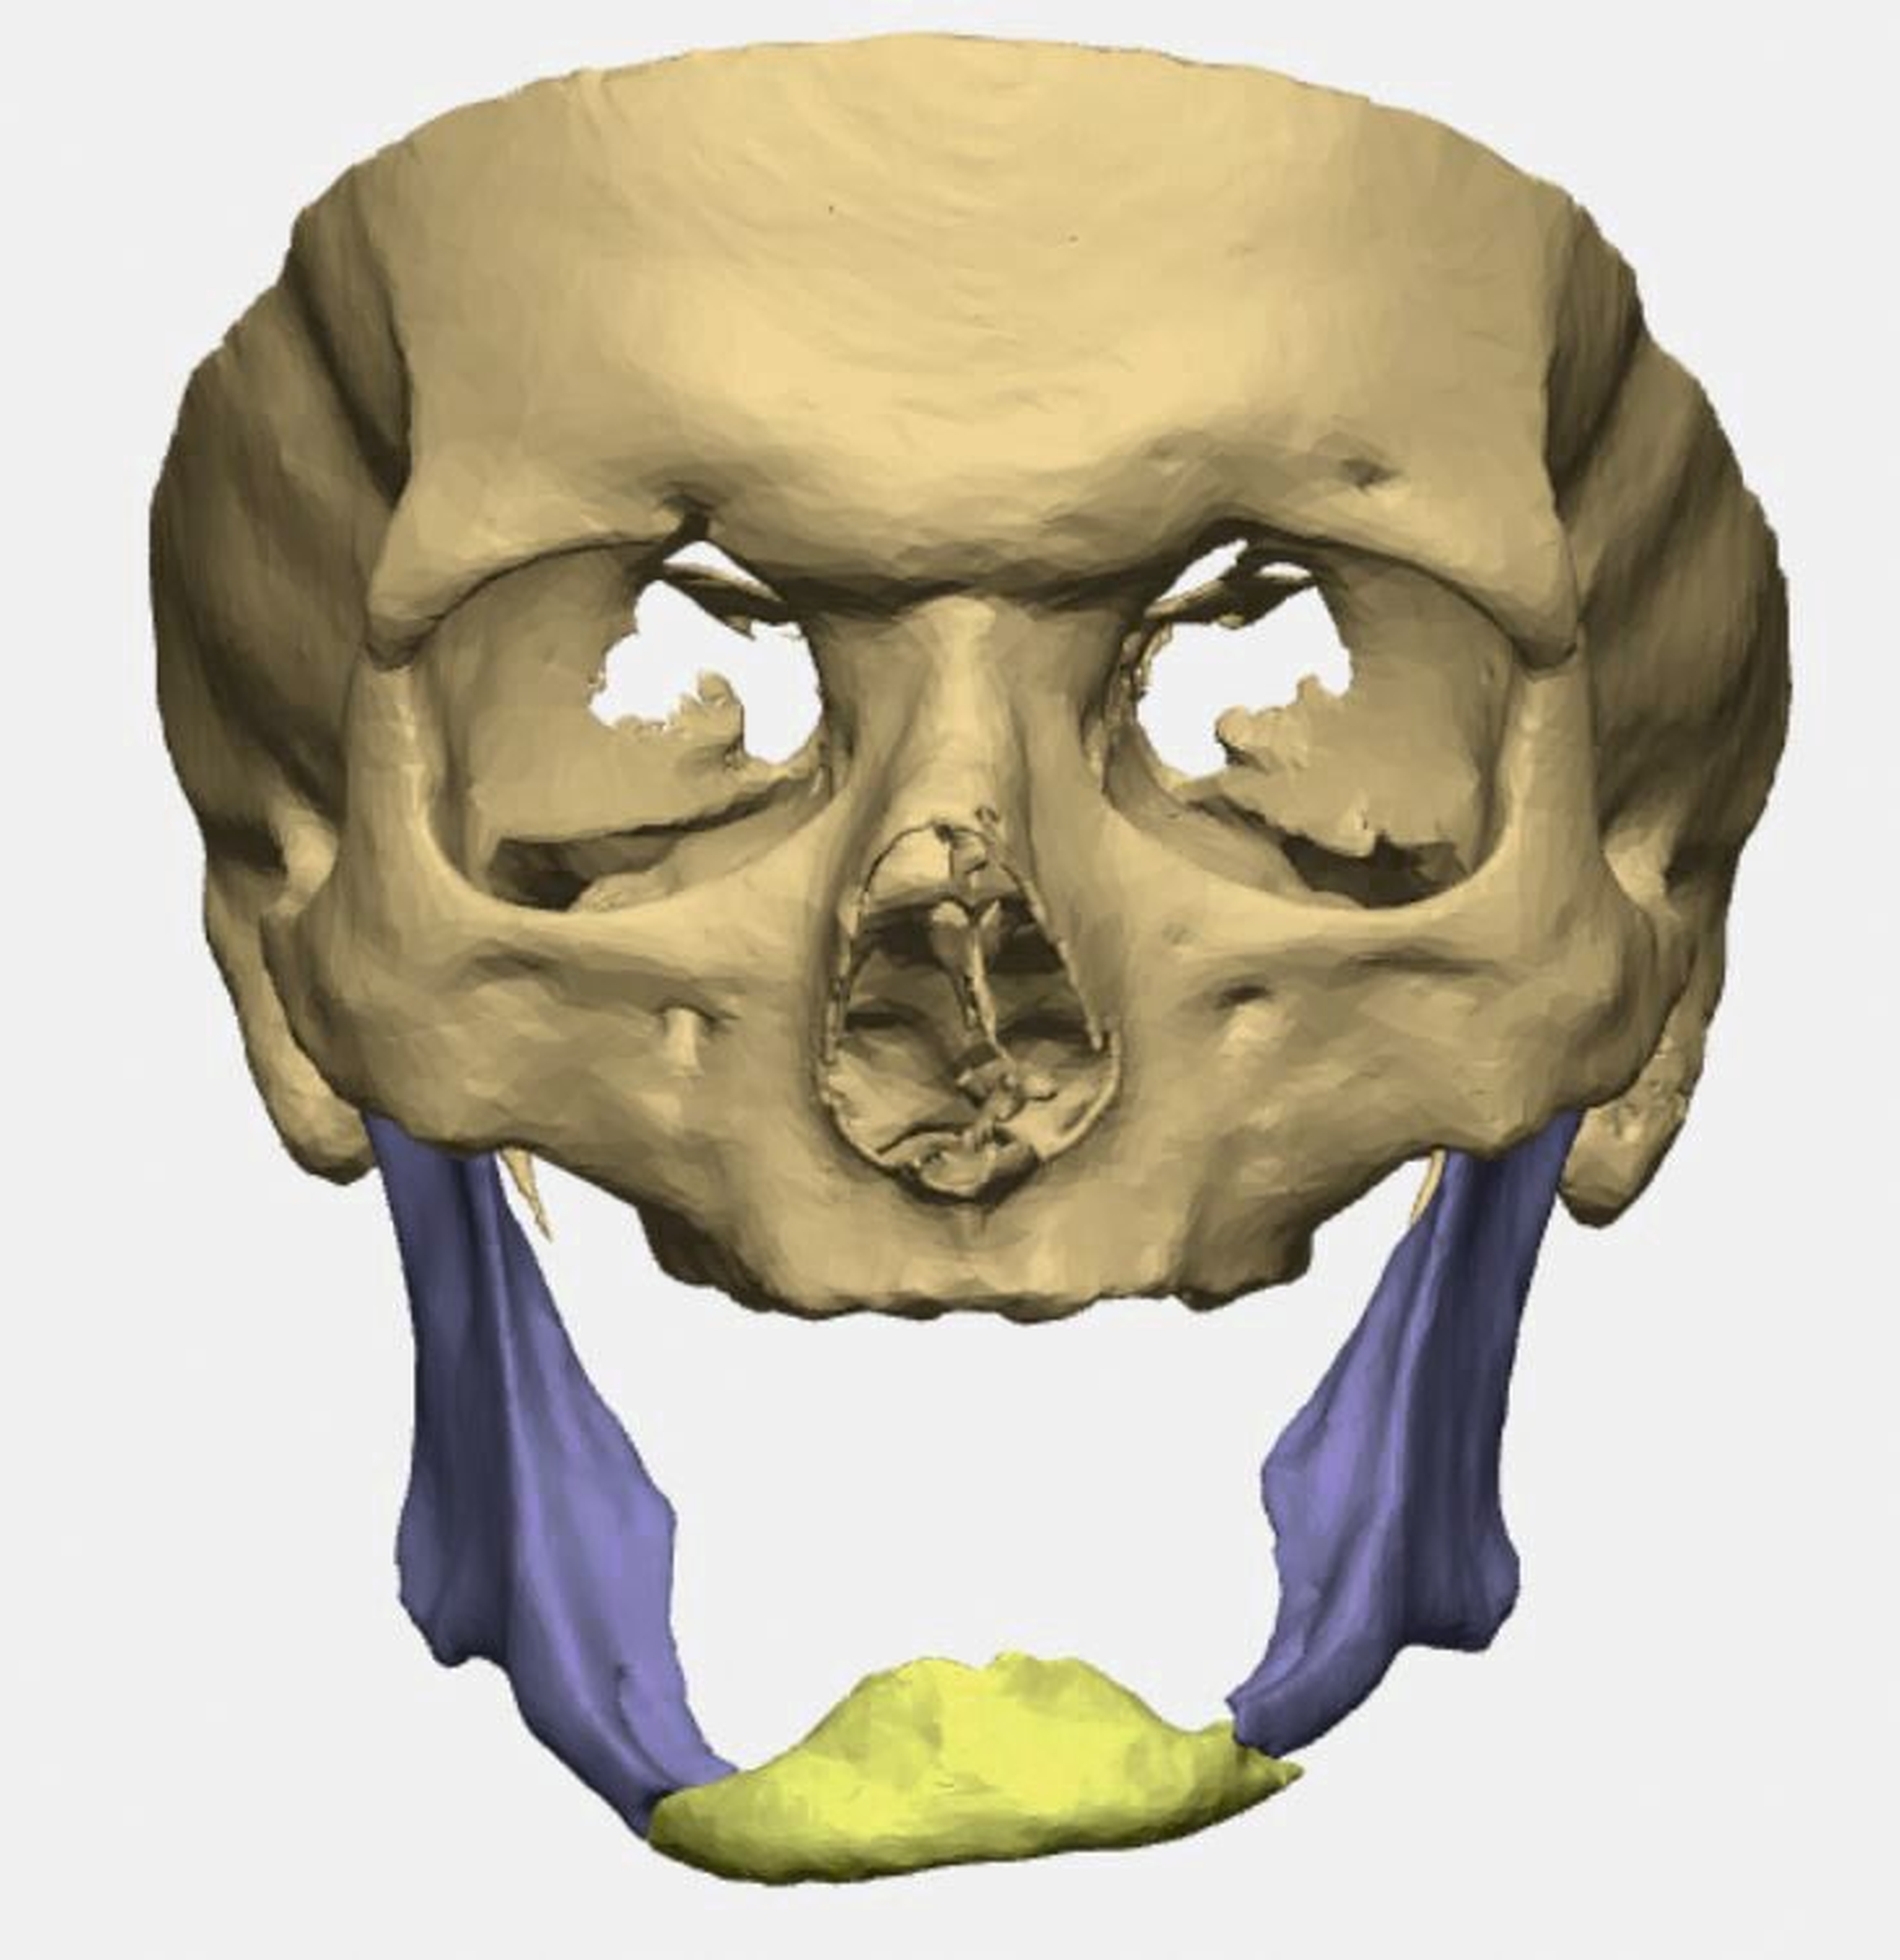

Bei zahnlosem Ober- und Unterkiefer erfolgte die virtuelle Repositionierung des frakturierten Unterkiefers (Abbildung 2a). Mittels CAD/CAM-Verfahren wurde eine stabile Rekonstruktionsplatte aus Titan (patientenspezifisches Implantat; PSI) geplant und hergestellt. Dabei sollte die Position des PSIs im Bereich des Unterkieferkorpus weit kaudal an der Basis sein, so dass später bei der Anpassung einer neuen Unterkieferprothese keine Interferenzen auftreten (Abbildung 2b).

Gleichzeitig konnte durch eine optimierte Bohrlochposition der Nervus alveolaris inferior geschont werden, eine Neurolyse brauchte nicht geplant zu werden. Außerdem wurden an die Zielreposition angepasste Bohrschablonen (drilling guides) hergestellt, die ein Vorbohren der späteren Schraubenlöcher in der exakten Zielposition ermöglichen (Abbildung 2c). In Kombination mit dem PSI sollte so eine Auto-Reposition des Unterkiefers durch die vorgegebenen Bohrlöcher erfolgen.

Durch einen frühzeitigen Zahnverlust im jungen Erwachsenenalter – zum Beispiel durch Trauma oder kariöse Zerstörung – kann es im Laufe des Lebens aufgrund der fehlenden Belastung durch das Kauen zu einer ausgeprägten Atrophie des Unterkiefers kommen. Dieser sogenannte Pencil Bone oder auch Bleistiftknochen neigt insbesondere bei gleichzeitig bestehender Osteopenie/Osteoporose zu einer Frakturierung bei schon geringen Traumaeinwirkungen. Dabei treten meist ein- oder beidseitige Unterkieferkorpusfrakturen auf. Bei beidseitigen Frakturen kann das mediane Bruchstück aufgrund des Zuges der Zungengrundmuskulatur nach kaudodorsal abgedrängt werden [Madsen et al., 2009].